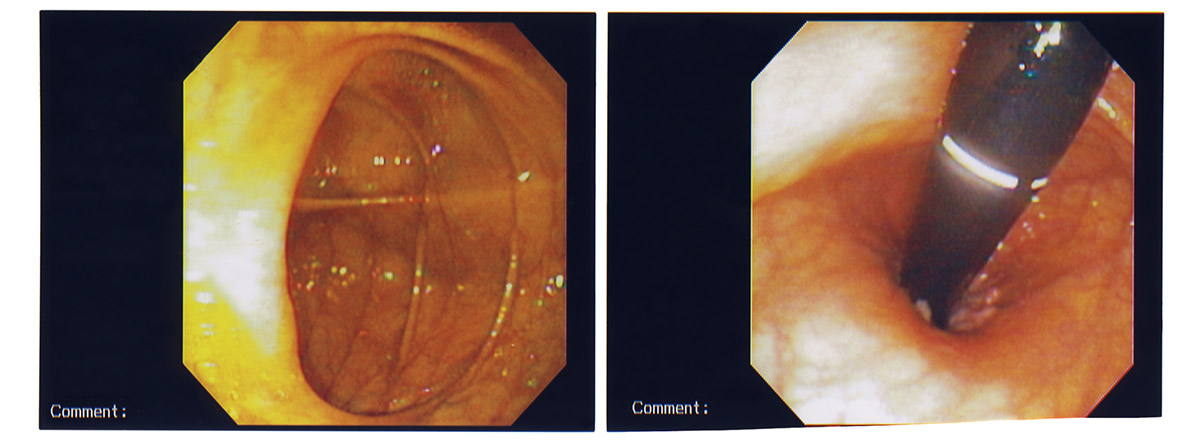

El endoscopio es una sonda flexible que lleva asociado una cámara de vídeo y que se encuentra conectado a un monitor y/o a un ordenador en el cual se proyectan o guardan las imágenes obtenidas durante el estudio.

Cuando se realiza un estudio de todo el intestino grueso hablamos de colonoscopia o endoscopia digestiva baja. Cuando se realiza un estudio únicamente de la porción final del intestino grueso (recto y sima) hablamos de rectoscopia o sigmoidoscopia.

El paciente deberá desnudarse de cintura para abajo, se le facilitará una bata o sábana para cubrirse. Permanecerá tumbado sobre un costado y con las piernas flexionadas hacia el abdomen durante todo el estudio. El médico realizará una exploración manual del recto y posteriormente procederá a la colocación del colonoscopio a través del esfínter anal. Insuflará una cierta cantidad de aire en el intestino para favorecer el avance del colonoscopio y permitir la visualización de su interior. Durante el estudio puede realizarse toma de secreciones (aspirado) o de tejidos (biopsia) si fuera necesario. Una vez finalizado el estudio se procederá a la retirada del colonoscopio.